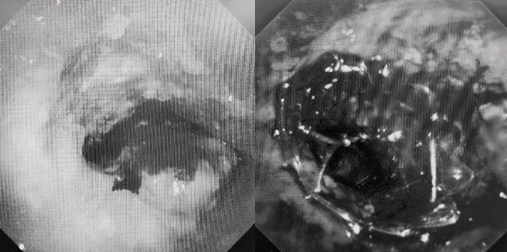

時(shí)間就是生命!了解患者病情后,歐陽(yáng)海峰立刻啟動(dòng)氣道梗阻緊急救治通道,協(xié)調(diào)院前轉(zhuǎn)運(yùn),急診快速入院流程。凌晨患者入院胸部CT顯示,現(xiàn)存唯一的呼吸通道在右主支氣管處,狹窄處僅約3毫米,患者命懸一線!

運(yùn)用呼吸介入技術(shù),軟硬鏡結(jié)合快速開(kāi)通氣道,是患者目前唯一可行的治療方案,手術(shù)刻不容緩!但存在麻醉后氣道完全塌陷閉合、大出血、窒息等巨大風(fēng)險(xiǎn)?;颊叽饲敖舆B轉(zhuǎn)診3家醫(yī)院,均建議保守支持治療或轉(zhuǎn)院。歐陽(yáng)海峰詳細(xì)了解患者病史,全面評(píng)估影像檢查結(jié)果后,決定盡快進(jìn)行手術(shù),組織醫(yī)護(hù)團(tuán)隊(duì)對(duì)患者進(jìn)行持續(xù)密切監(jiān)測(cè),充分保障其術(shù)前安全。

患者入院第二天,在麻醉手術(shù)中心全力配合下,歐陽(yáng)海峰帶領(lǐng)呼吸介入團(tuán)隊(duì),歷時(shí)40分鐘快速置入硬質(zhì)支氣管鏡、鏟切腫瘤,并順利植入全覆膜TTS支氣管金屬支架?;颊邭舛贪Y狀即刻緩解,為患者贏得了寶貴的后續(xù)治療機(jī)會(huì)。